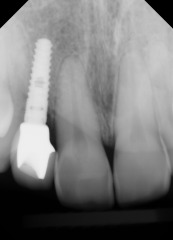

Charles P.

This patient had an Implant placed to replace a missing molar which had been removed due to infection.